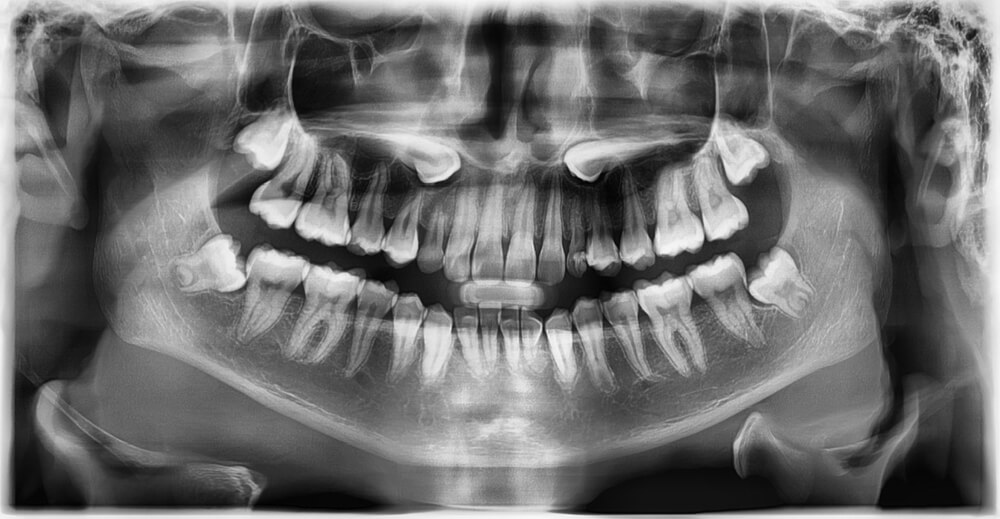

Gömülü dişlerin tedavisi, dişin pozisyonuna ve hastanın semptomlarına bağlı olarak değişir. İlk olarak, diş hekiminiz detaylı bir muayene ve röntgen ile dişin konumunu belirler. Eğer gömülü diş herhangi bir ağrı veya enfeksiyona neden olmuyorsa, belirli bir süre boyunca takip edilebilir. Ancak, ağrı, enfeksiyon veya diğer dişlere zarar verme riski varsa, cerrahi müdahale gerekebilir. Bu işlem genellikle lokal anestezi altında yapılır ve diş eti kesilerek diş çıkarılır. Cerrahi işlem sonrası, iyileşme süreci dikkatli bir şekilde izlenmeli ve hekimin önerdiği bakım talimatlarına uyulmalıdır.

Gömülü dişlerin tedavisi, dişin konumuna ve hastanın semptomlarına bağlı olarak değişir. Diş hekimi, detaylı bir muayene ve röntgen ile dişin pozisyonunu belirler. Eğer gömülü diş ağrı veya enfeksiyona neden olmuyorsa, düzenli kontrollerle takip edilebilir. Ancak ağrı, enfeksiyon veya diğer dişlere zarar verme riski taşıyorsa, cerrahi müdahale gerekebilir. Bu işlem genellikle lokal anestezi altında yapılır ve diş eti kesilerek diş çıkarılır. Cerrahi işlem sonrası iyileşme süreci dikkatle izlenmeli ve hekimin önerdiği bakım talimatlarına uyulmalıdır.

Gömülü diş tedavisi, dişin konumu, hastanın yaşadığı belirtiler ve dişin çevresindeki dokuların durumuna bağlı olarak değişir. İlk adım, detaylı bir muayene ve röntgen çekimi ile dişin pozisyonunun belirlenmesidir. Eğer gömülü diş herhangi bir ağrı veya enfeksiyona neden olmuyorsa, diş hekimi düzenli takipler ile durumu izleyebilir. Ancak ağrı, enfeksiyon veya komşu dişlere baskı gibi sorunlar mevcutsa, cerrahi müdahale gerekebilir.